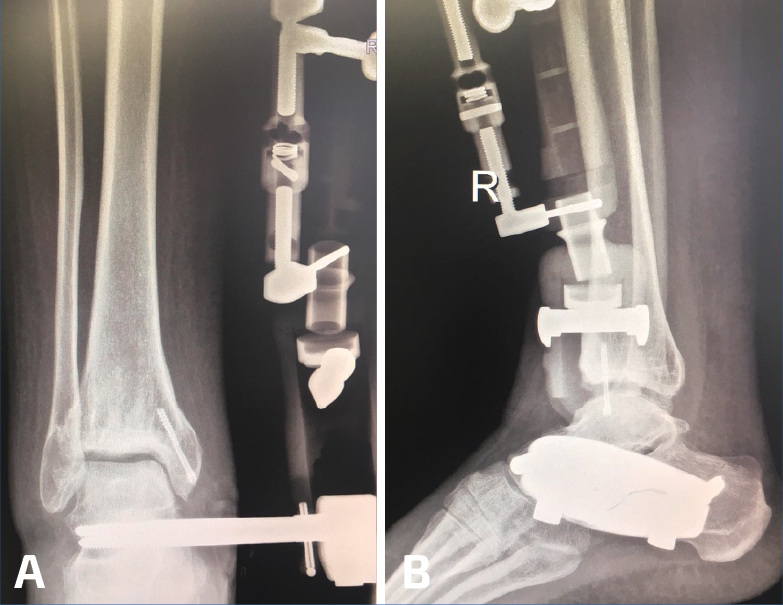

Figura 4. A y B: radiografías anteroposterior y lateral del fijador implantado con la distracción conseguida a nivel articular.

Utilizamos el fijador articulado monolateral (de tipo X-Caliber®, Orthofix). En un primer paso procedemos a colocar los pines en astrágalo y calcáneo mediante la guía radiotransparente (Figura 2), para posteriormente colocar los pines tibiales en la superficie anteromedial de la misma (a ser posible 3). Al acabar el procedimiento procedemos a realizar progresivamente una distracción de entre 7 y 8 mm (se dispone de un calibrador en el fijador que nos permite visualizar la distracción que estamos realizando) (Figura 3) bajo control radioscópico, dejando finalmente la pieza articulada totalmente libre para la movilidad tibioastragalina desde el principio. Aplicamos un vendaje compresivo de la extremidad y retiramos la isquemia (Figuras 4 y 5).